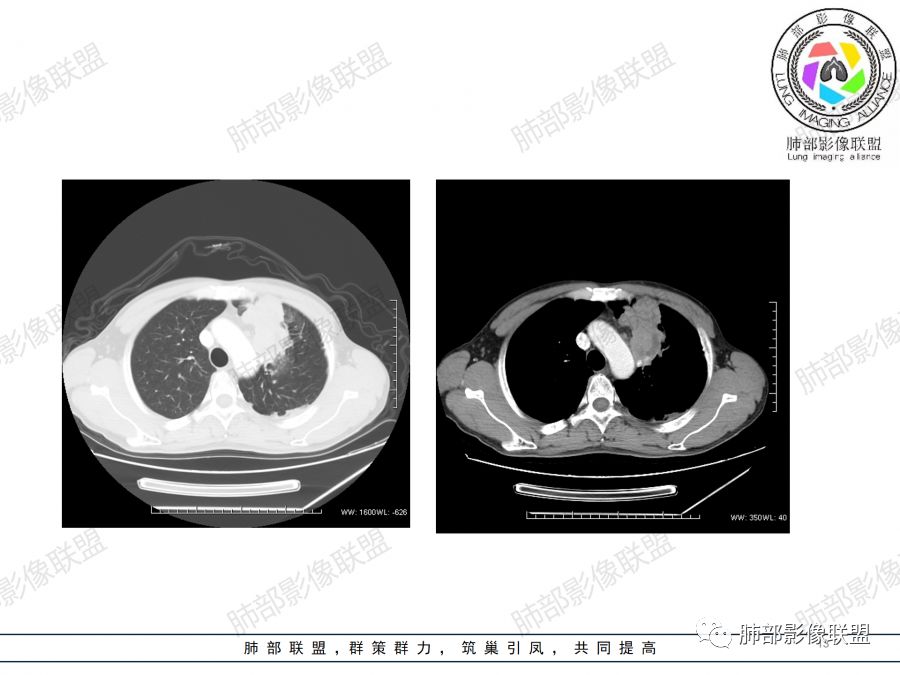

左肺上叶见不规则肿块影,可见分叶,边缘膨隆部分边缘平直,增强后病灶可见不均匀明显强化,内见血管影,其血管边缘不光滑,周围肺野可见小结节病灶,考虑恶性病变,肿块与支气管关系显示不清,需要薄层,从肿块边缘平直来看应该有阻塞性肺炎和肺不张,偏向鳞癌。

男性,47岁,咳嗽咳痰一月。

胸CT:左上叶前段团块影,边缘部分清晰,近纵隔侧膨隆明显,分叶,肺侧见平直征,U形凹陷,病灶周围可见磨玻璃影,气肿带,纵隔多发淋巴结肿大,叶间裂多发小结节。增强病灶内密度不均,散在斑片状低密度区,血管造影征。考虑:恶性,鳞?腺?大细胞?鉴别:炎症。似有左侧胸廓内A供血病灶,SFT?

和风徐徐:

男,47岁,咳嗽咳痰一月余入院肺气肿背景。左上肺纵隔旁非均质肿块,分叶、膨隆,部分边缘光滑,肺门可见冰冻征,增强不均匀强化,见沼泽地样坏死,邻近肺组织见斑片状炎症,考虑恶性肿瘤,首先考虑小细胞癌,鉴别鳞癌。

傅昌瑜:

47岁男性,咳嗽咳痰1月余。左肺上叶结节灶,形态不规则,边缘见分叶,其内可见斑片状低密度区。增强扫描呈轻度强化,侵犯纵隔及部分胸膜,综合考虑恶性!

弹指之间:

中年男性,左肺上叶肿块、片状状影,形态不规则,边缘见分叶及磨玻璃影,其内可见斑片状低密度区及血管穿行。增强扫描呈轻度强化,侵犯纵隔及部分胸膜,纵隔见多发淋巴结肿大,定位:肺内,左上肺部分有不张;定性:偏恶性,侵犯支气管(病灶内见条状低密度影)但血管无明显受累,考虑粘膜相关性淋巴瘤(粘膜下起源)可能,结核待排;腺癌、鳞癌(血管无受侵不首先考虑),小细胞(无典型表现、虽然血管保留可见于小细胞);